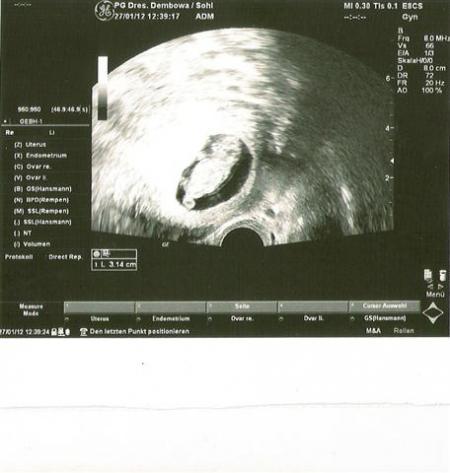

So ihr Lieben, danke fürs viele Daumen drücken, hat bei mir jedenfall geholfen. Mein Krümel ist jetzt 3,14 cm groß und das Herzchen schlägt super. Ganz verschlafen der/die KLEINE, hat sich nicht wecken lassen, aber hauptsache es geht ihm gut. Juhu, freu mich sehr.

Ja ein ganz süßes Bildchen

Bild zu